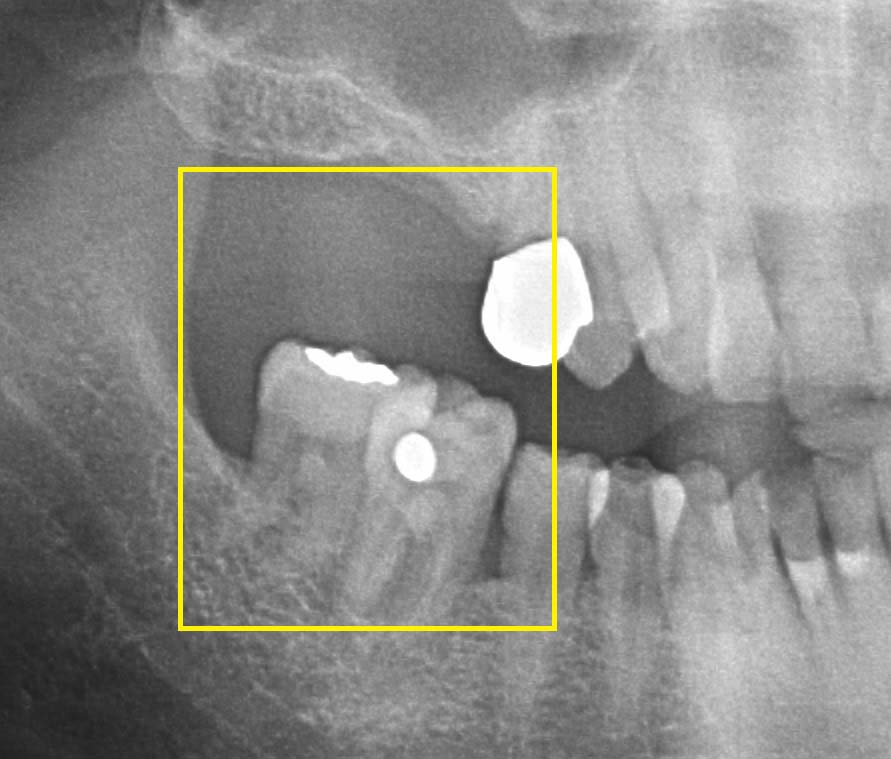

대표적인 치료 방법인 임플란트는 인공 뿌리를 심고 그 위에 치아 머리를 수복하는 것으로, 주변 치아의 손상 없이 구조를 복원할 수 있다. 임플란트 치료 기간은 발치 후 임플란트를 심기 전까지 대기시간과 임플란트를 심은 후 상부 보철물을 씌우기까지 대기시간에 따라 결정된다. 전통적인 과정은 발치 후 3~4개월을 기다려 치아 뿌리가 있던 공간에 뼈가 어느 정도 차면 임플란트를 심는 방식이다. 이후 3개월 이상 지나서 뼈와 임플란트가 완전히 붙으면 보철물을 씌운다. 백연화 교수는 “최근에는 임플란트 디자인, 표면 처리 방법 외에도 수술 기법 등이 발달해 6~8주로 치료 기간이 짧아지는 추세”라며 “제한적인 경우에 한해 발치 당일 임플란트 수술과 임시 보철물까지 즉시 연결하기도 한다”라고 말했다.